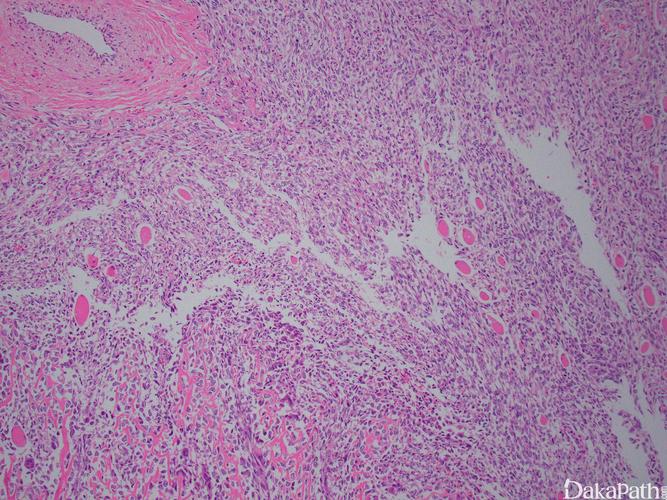

骨肉瘤切片

骨肉瘤切片,骨肉瘤图片